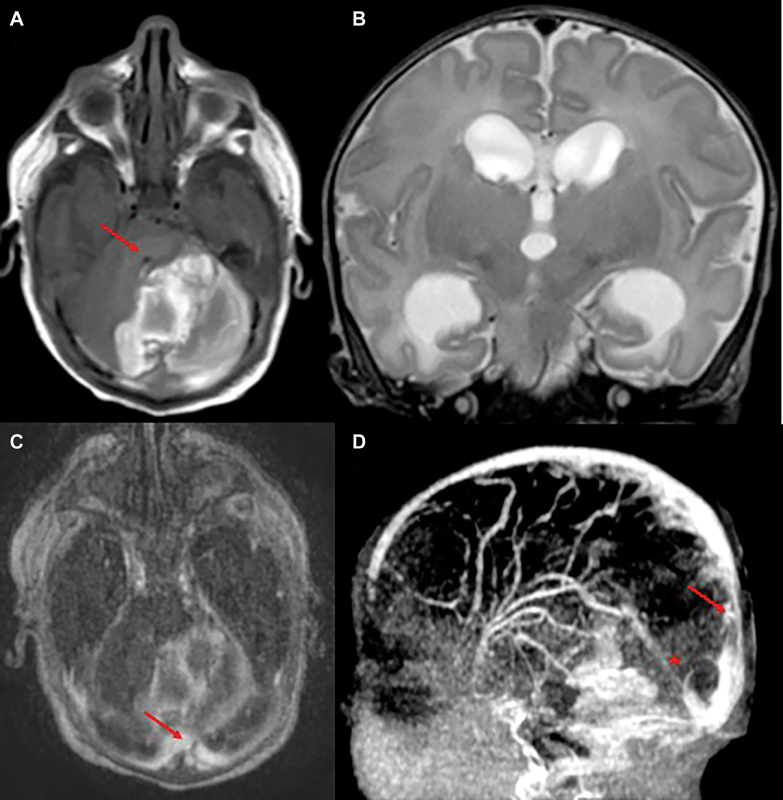

Study design: We report the case of a full-term neonate diagnosed with CSVT, highlighting the rationale for early anticoagulation with unfractionated heparin. A brief literature review supports our clinical decision-making, considering current evidence and expert consensus despite limited neonatal-specific guidelines.

Results: Heparin therapy was started shortly after diagnosis, without hemorrhagic complications. Neuroimaging showed complete thrombus resolution. The neonate had a normal neurological examination at discharge. Follow-up confirmed overall good clinical condition and showed mild axial hypotonia and convergent strabismus suggestive of cortical visual impairment.